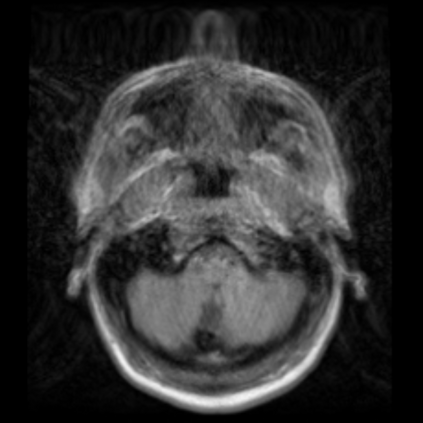

Motion artifacts are a primary source of magnetic resonance (MR) image quality deterioration with strong repercussions on diagnostic performance. Currently, MR motion correction is carried out either prospectively, with the help of motion tracking systems, or retrospectively by mainly utilizing computationally expensive iterative algorithms. In this paper, we utilize a novel adversarial framework, titled MedGAN, for the joint retrospective correction of rigid and non-rigid motion artifacts in different body regions and without the need for a reference image. MedGAN utilizes a unique combination of non-adversarial losses and a novel generator architecture to capture the textures and fine-detailed structures of the desired artifacts-free MR images. Quantitative and qualitative comparisons with other adversarial techniques have illustrated the proposed model's superior performance.

翻译:移动文物是磁共振(MR)图像质量恶化的一个主要来源,对诊断性能产生强烈影响。目前,MR运动的校正要么是预期性的,借助运动跟踪系统,要么是追溯性的,主要是利用成本昂贵的计算迭代算法。在本文中,我们使用名为MedGAN的新颖的对抗性框架,联合追溯性地校正不同身体区域的硬性和非硬性运动文物,而不需要参考图像。 MedGAN利用非对抗性损失和新型生成器结构的独特组合来捕捉无MR图象的纹理和精细详细结构。 与其他对抗性技术的定量和定性比较展示了拟议模型的优异性表现。